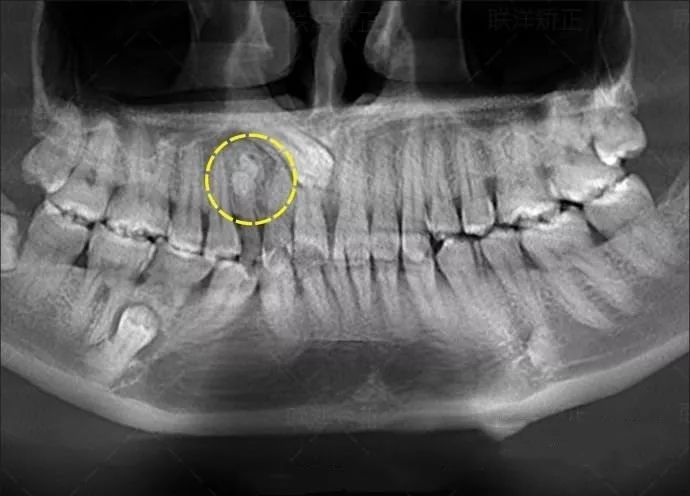

患者是30多岁的年轻男子,红色标记那颗牙松动,要求拔牙,开始嫌麻烦不愿拍片,后来经过再三劝说还是拍了片。结果把所有人包括他自己都吓了一跳。估计是良性,具体还得去医院住院手术做病理检查,所以大家不要忽视一张片子带来辅助检查的重要性。

试想,如果没有拍片,直接贸然拔牙,一旦出现问题......一张牙片,“救”了诊所,也救了患者!

通过x线片不仅能了解牙齿本身的病变情况,还可以了解牙根下有没有囊肿、周围骨头有没有吸收以及牙槽骨内是否有埋伏牙、多生牙等。依据X线片综合分析,可以提高齿科医生诊断治疗牙齿的准确性和成功率。

由于牙齿下部隐藏在牙槽骨中,口腔医生要了解牙齿的整体情况就需要拍摄全景片;要了解个别牙根及周围变化,则选择拍摄小牙片。